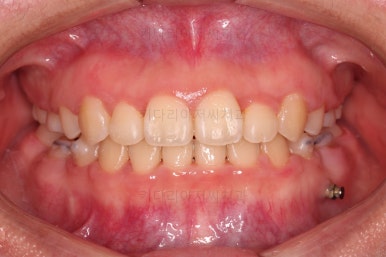

이원교정을 하신지 총 30개월 만에 남아있던 유치 자리가 잘 다물어졌고요.

이 뽑은 자리도 잘 메워졌고, 앞니도 가지런해졌어요.

위아래 치아 갯수도 동일하게 교합도 잘 맞췄고요.

예상보다 빠른 기간 안에 매우 만족스러운 치료였어요.

부산재교정 전후사진을 비교해 볼게요.

치열의 모습이 참 좋아졌고, 입매도 본인이 원하는 수준까지 좋아졌어요.

처음부터 환자분과 맞는 치과를 잘 선택하셨다면 덜 고생을 하셨을텐데, 그래도 매우 만족스러운 부산재교정 치료결과였어요.